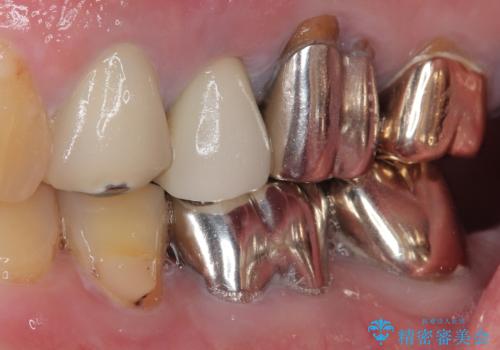

破折した奥歯 抜歯即時埋入インプラントによる補綴治療

- 舌側に膿の出口がずっと消えずに有り続けることを気にして来院された患者様です。

目視で歯根が破折していることが分かり、保存不可能と判断されたたため、抜歯即時埋入インプラントによる補綴治療を行うこととしました。